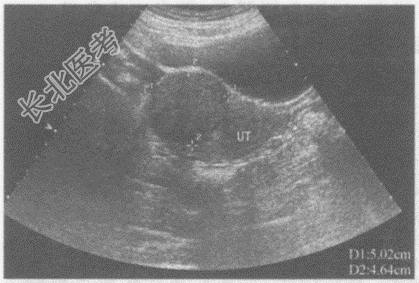

- 单项选择题临床资料:女性, 40岁,常规体检。超声综合描述: 子宫前位,宫底右前壁可见5.0cm×4.6cm稍低回声区, 边界清晰,形态规则, 内回声尚均匀,向包膜外突起, CDFI:稍低回声区内及周边可见丰富动静脉血流信号。见下图及彩图。其超声提示: